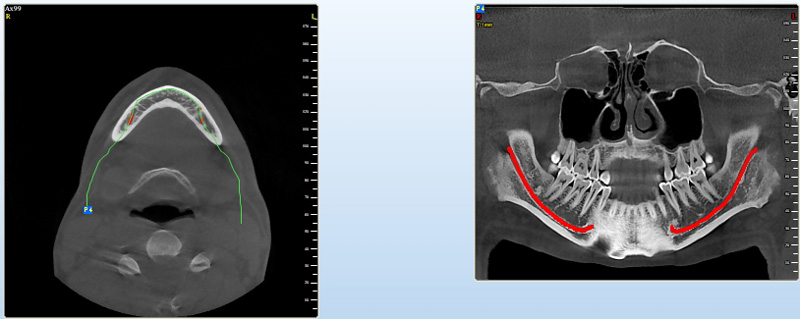

Pomocí tohoto přístroje je možné zjisti skutečnou situaci v čelistních kostech pacienta tedy množství kosti - můžeme změřit skutečnou šířku i výšku kosti, i kvalitu kosti (hustotu) v místě uvažované implantace. 3D (tříprostorové) zobrazení umožňuje

zvýšit prostorovou představu operatéra ještě před vlastní operací a zároveň pacientovi lépe objasnit a ukázat oblast plánovaného zavedení implantátu.

Pacient „neumí číst“ RTG snímky, ale díky 3D zobrazení vidí „svoji skutečnou čelist“ – např. jak je nízká či úzká, vidí průběh nervu nebo velikost čelistní dutiny, což mu umožní i pochopení nutnosti v některých případech provést pomocné zákroky

ještě před vlastním zavedením implantátu (více - Augmentace - kostní štěp, sinus lift, kostní granulát...).

Pomocí počítačových programů – NewTom Implant Planning a coDiagnostiX si lékař sám provádí veškerá potřebná zobrazení a měření.

Lékař si vytvoří všechny typy zobrazení potřebných pro naplánování – tedy 2D snímky (panoramatický), příčné řezy i 3D model.

Vidí zde i důležité anatomické útvary – čelistní dutinu, průběh nervu atd. Po proměření množství kosti – šířky i výšky vybere z databáze vhodný typ implantátu a umístí ho do požadované lokality.

Ihned vidí jeho pozici ve všech 3 rovinách a na všech snímcích i 3D modelu. Může upravovat podle potřeby jeho pozici, sklon atd.